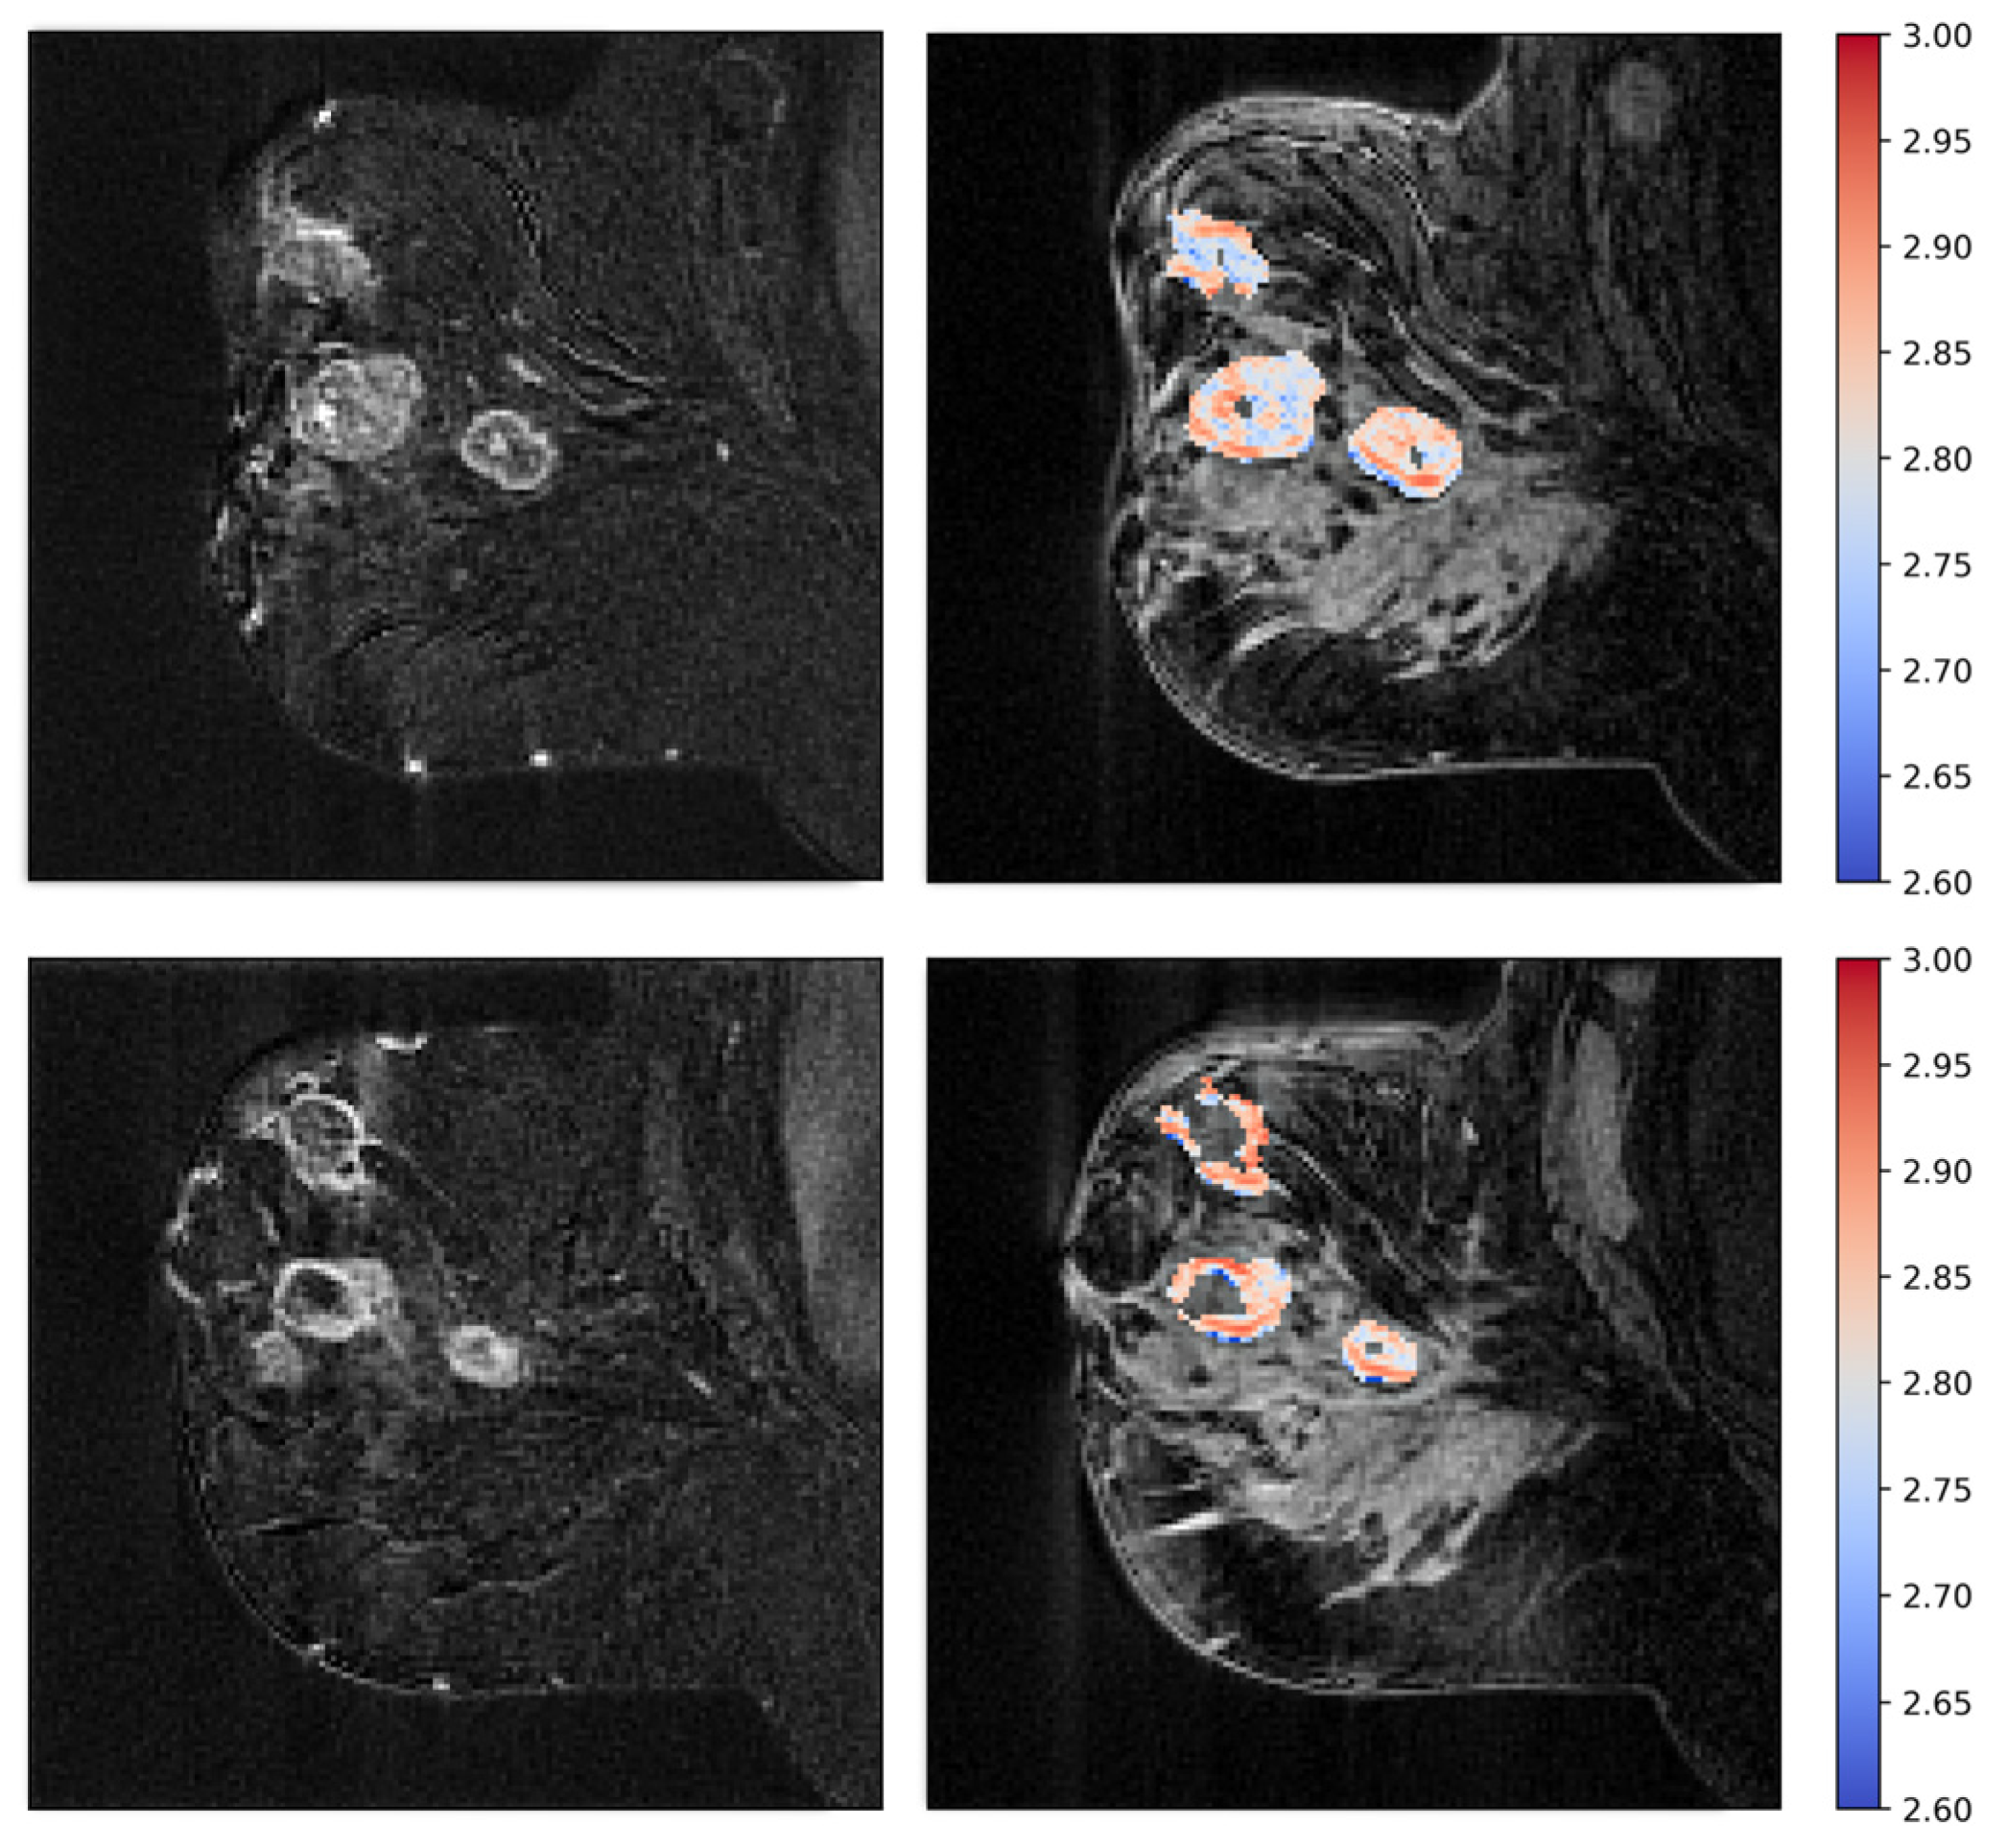

Figure 6.

Patient treated with bevacizumab showing intermediate pre-treatment fractal dimension (top), with a significant increase in fractal dimensionality after one week of treatment (bottom). The fractal dimension maps are shown to the right as colored overlays on T2-weighted images. To the left are the subtraction images that the fractal dimension is calculated from.

Figure 7.

Patient treated with bevacizumab, showing high pretreatment fractal dimension (top), with a significant reduction after one week of treatment (bottom). Fractal dimension maps are shown to the right, and subtraction images are shown to the left.